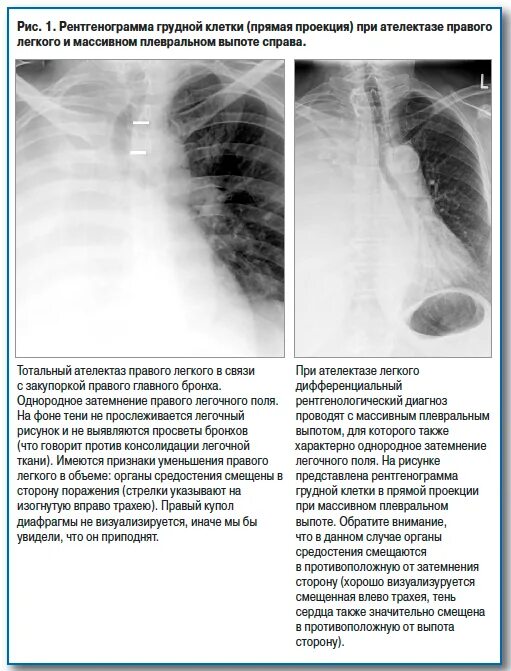

Шаблоны описания рентгенограмм